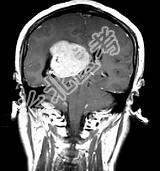

- 单项选择题女,45岁, 右眼视力下降8个月,右颜面麻木半个月, 时有头昏,味觉减退, 请根据所提供图像,选择最可能的诊断是 ( )

A、(右侧脑室)胶质瘤

B、(右侧脑室)脉络膜乳头状瘤

C、(右侧脑室)转移瘤

D、(右侧脑室)室管膜瘤

E、(右侧脑室)脑膜瘤(合体细胞型)